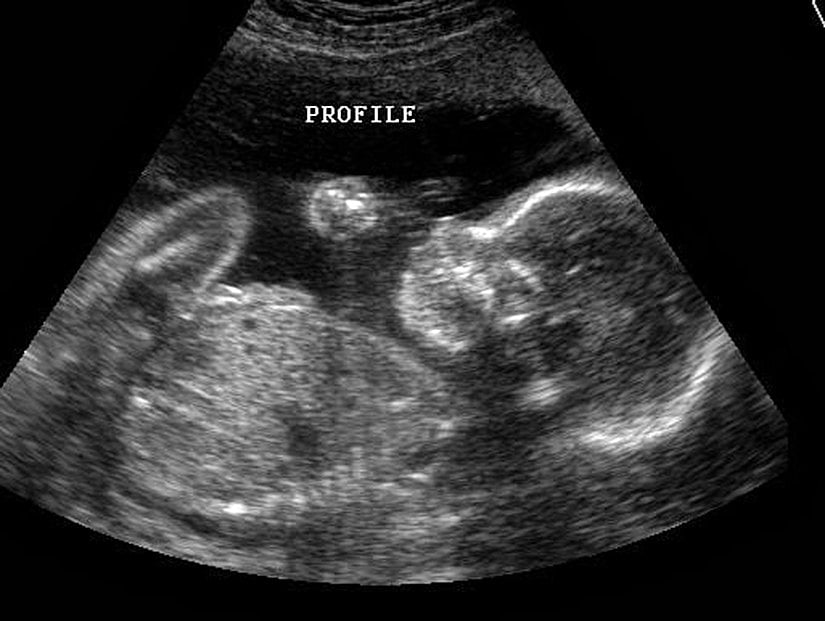

Genellikle ebeveynler, yavrularının ilk fotoğraflarını oldukça bulanık ve çoğu zaman pek bir şey anlaşılmaz bir şekilde alırlar. Çünkü ultrason teknolojileri sadece siyah-beyaz ve oldukça fazla gürültülü (alınmak istenen sonucu etkileyen sinyalli) sonuçlar verir. Tipik bir örneği şöyledir:

2 boyutlu ultrason görüntülerinde, duyabileceğimiz frekansın üzerindeki ses dalgaları gönderen bir çubuk, karna veya vajina içerisine konularak vücudu bu ses dalgalarıyla tarar. Bebeğin vücudundan ve annenin iç organlarından farklı şekillerde yansıyan ses dalgaları, sonradan bilgisayar yardımıyla fotoğrafa dönüştürülür ve böylece bebeğin bir kesiti oluşturulur. Doppler fetal ultrason yöntemindeyse, benzer bir ultrason cihazı kullanılarak bebeğin kalp atışları da tespit edilir ve yine bir bilgisayar yardımıyla bu sinyaller güçlendirilerek, annenin ve hekimin işitebileceği düzeye yükseltilir.